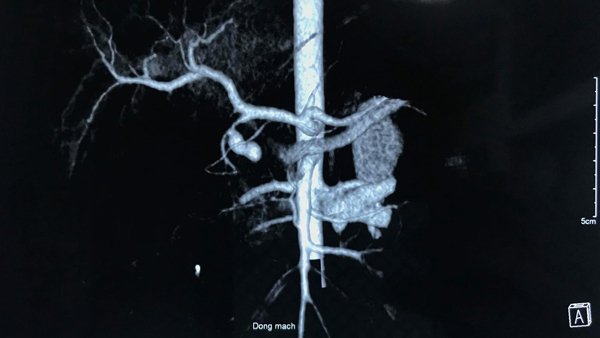

Gần 300 bệnh nhân can thiệp mạch vành thành công khi đặt stent do Việt Nam sản xuất, giá rẻ hơn hàng nhập khẩu 40%.